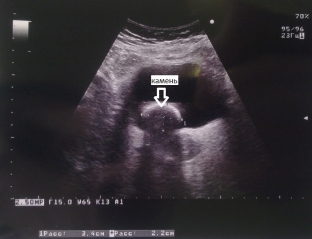

Highly informative ultrasound examination for urolithiasis

One of the most informative methods for diagnosing urolithiasis is ultrasound. Ultrasound examination allows to determine the characteristic acoustic signs of stones of the renal calyces and pelvis: stones give a strong echo signal, an acoustic cylindrical or conical shadow is formed behind the stone, the intensity of which depends on the composition and size of the stone. Coral-like stones on ultrasound have the appearance of an echogenic structure that repeats the shape of the pelvicalyceal system, completely or partially filling it. It is important to take into account the fact that ultrasound allows you to see stones larger than 3 mm.